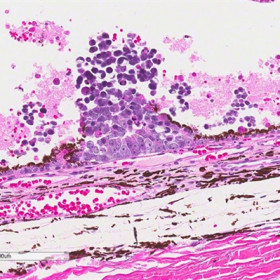

Retinoblastoma associated iris neovascularization

Retinoblastoma associated iris neovascularization (low and high power). Courtesy of Tatyana Milman, MD